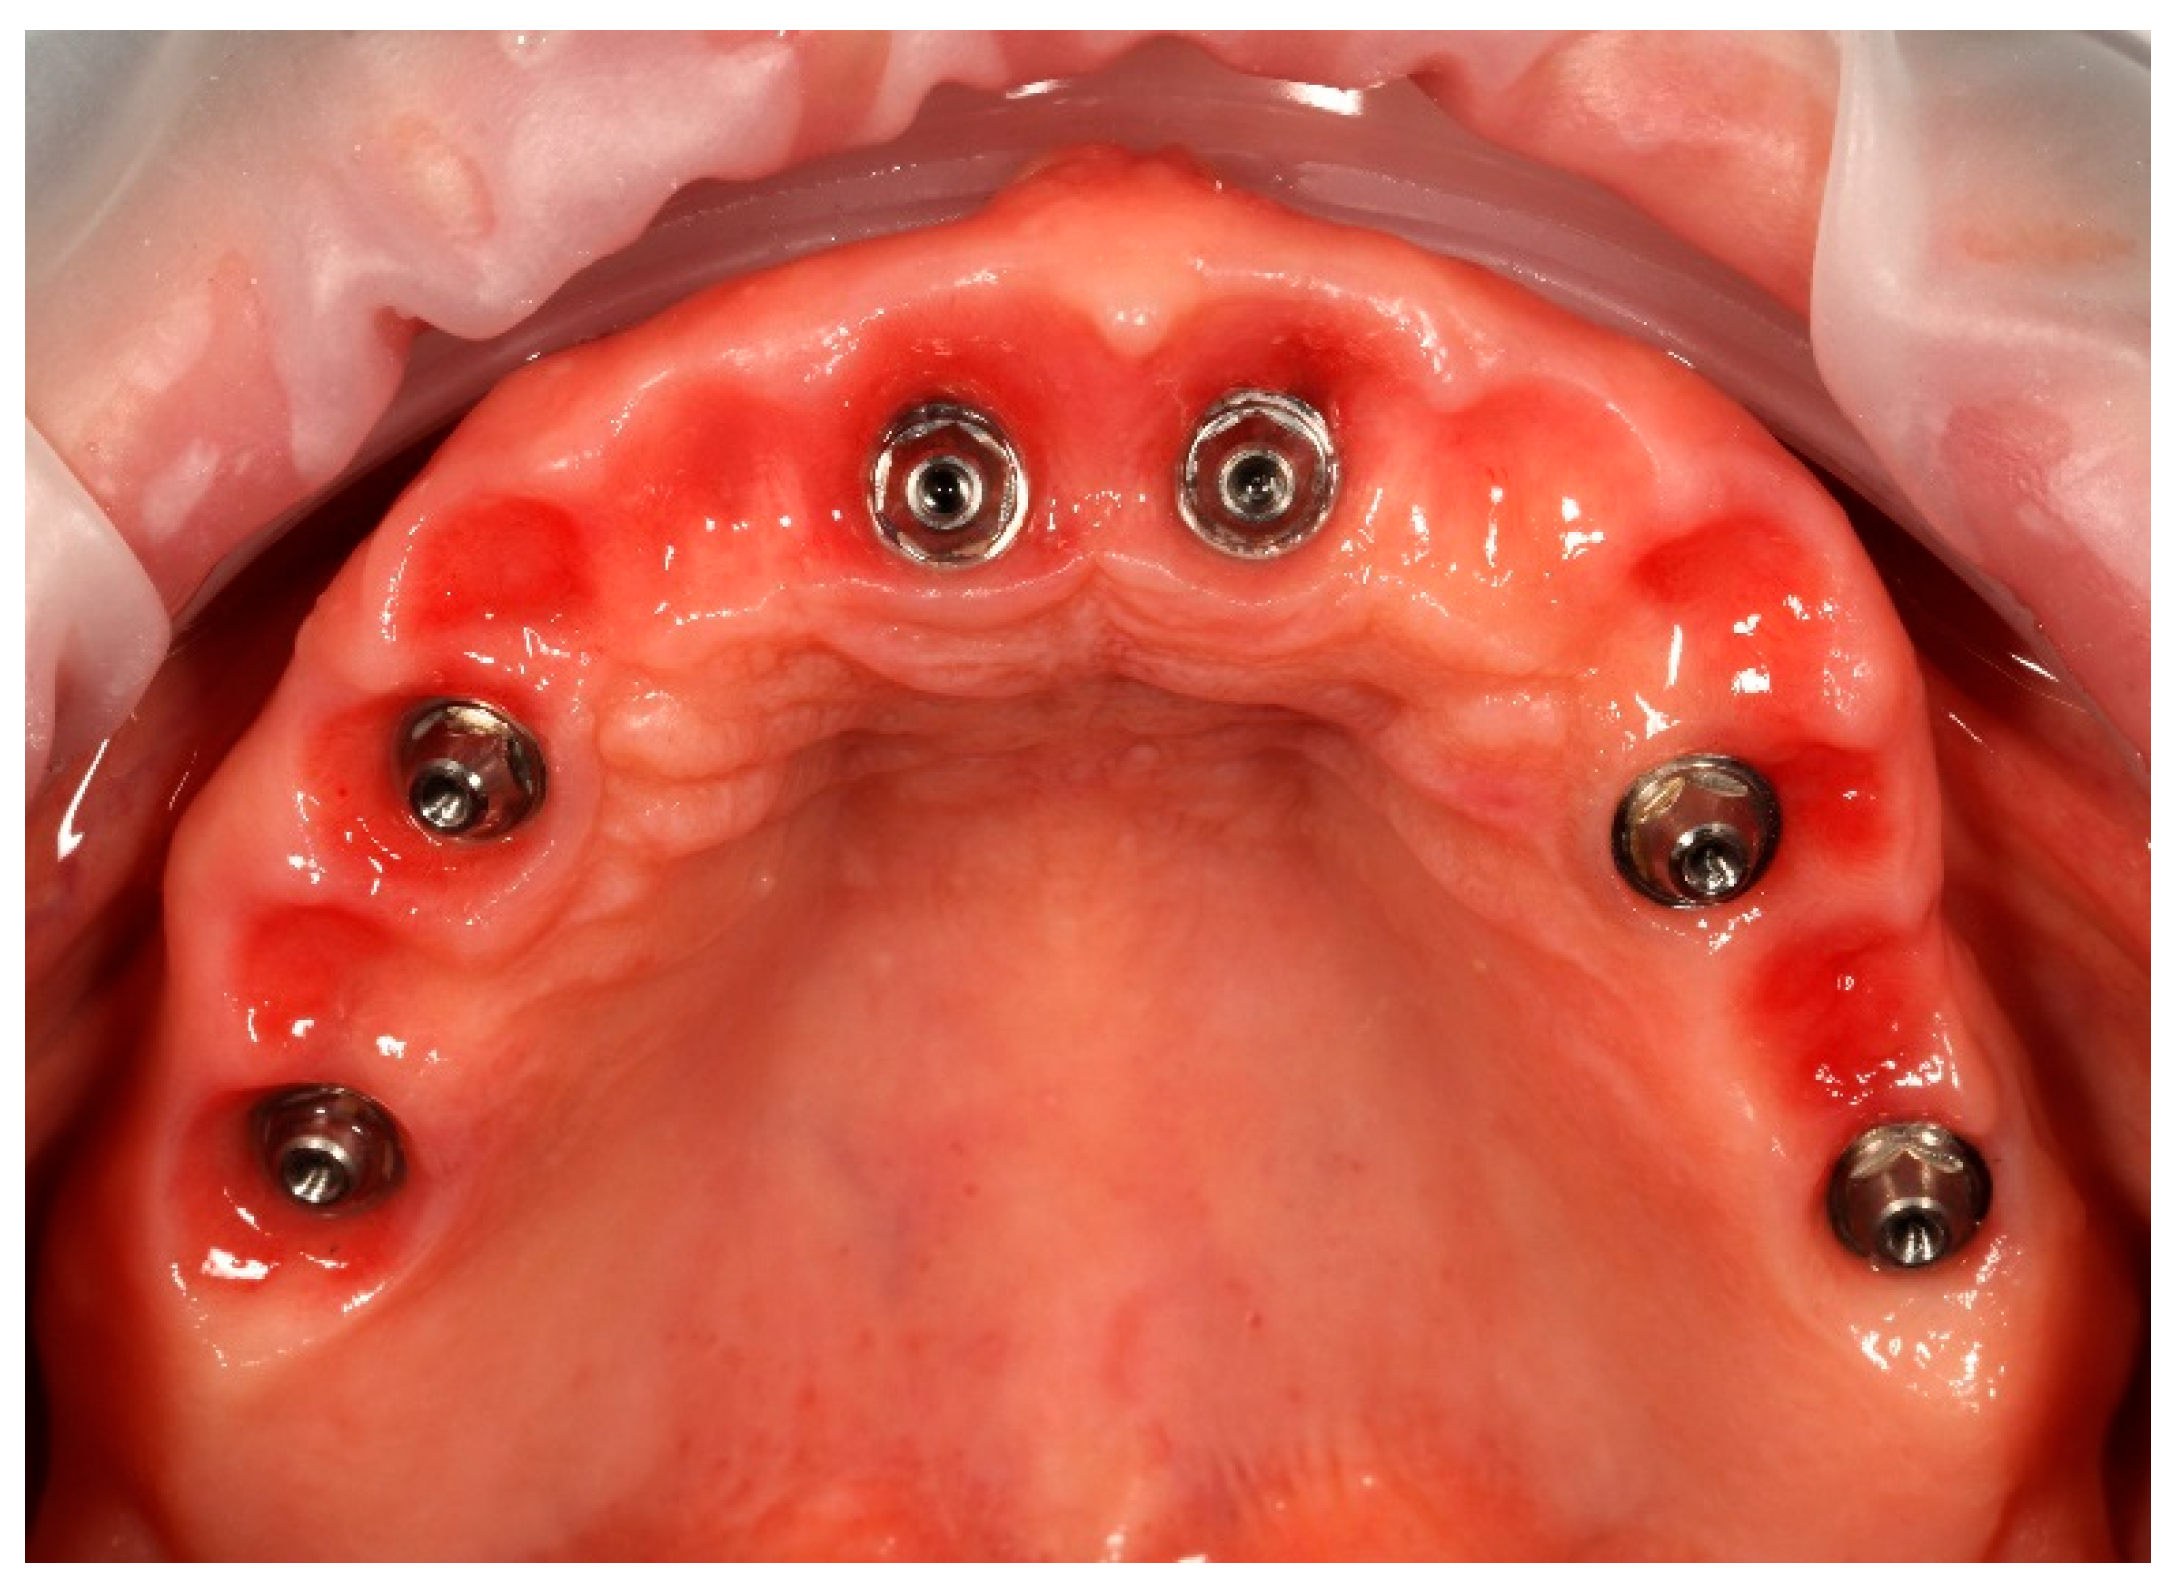

Upon removal of the provisional bridge from the multi-unit abutments, well-conditioned soft tissues were observed, adequately shaped by ovate pontics and corresponding to the requirements of the FP1-type full-arch prosthesis (Figure 13). No signs of inflammation or adverse response were noticed. As highlighted in the literature, provisional restorations are considered crucial for conditioning peri-implant soft tissues, as they help to establish the emergence profile and papillae prior to the definitive prosthesis being fitted [20].

Figure 13. Multi-unit abutments in situ after the removal of the provisional bridge, showing well-healed peri-implant soft tissues contoured by the pontics of the temporary restoration.